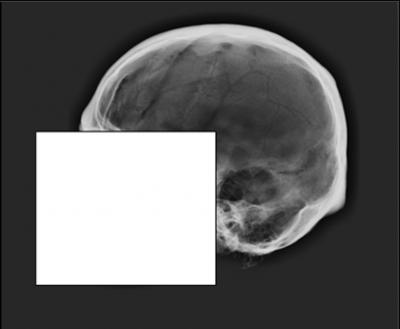

At issue is the "cranial vault outline," not the "face" of the skull. The cranial vault outline is the profile of the skull when viewed from the side, running from just above the bridge of the nose to the point where the skull and neck meet.

For the study, the researchers surveyed 106 members of the American Academy of Forensic Sciences. Survey participants were asked to evaluate 14 antemortem X-rays and five postmortem X-rays. Participants were then asked to match the 5 postmortem X-rays with the appropriate antemortem X-ray, effectively establishing a positive ID.